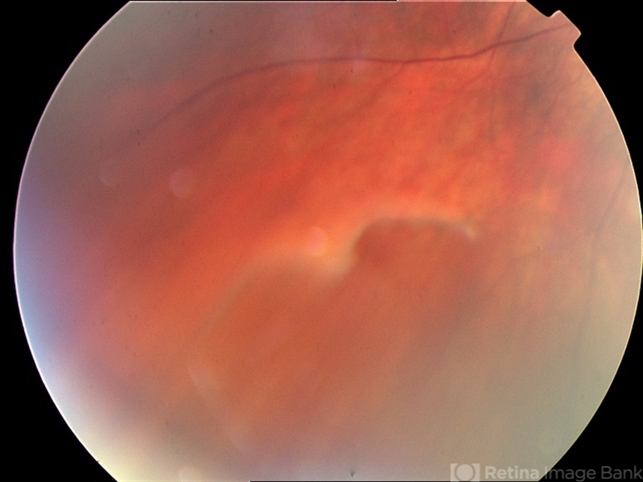

- Retinoschisis

- outer leaf break, inferotemporal retinoschisis

- Asymptomatic hyperope with non-progressive lesion for 10 years